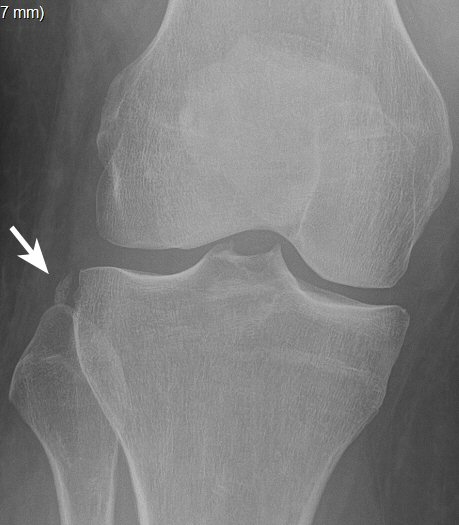

Segondfraktur: avulsionsfraktur lateralt av laterala tibiakondylen, är ofta associerad med ruptur av främre korsbandet.

Segondfraktur i högerknä